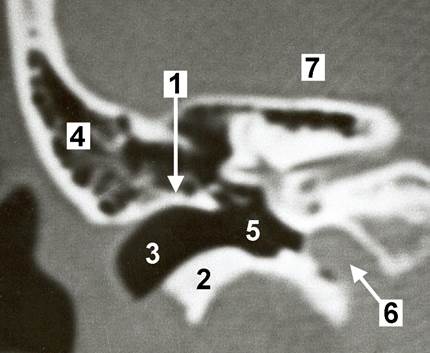

КТ анатомия сосцевидного отростка: особенности и показания